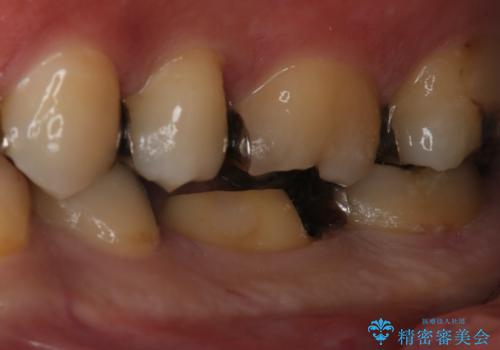

- 左下6番の銀歯が不適であったためやり変えを勧めたところセラミックでの治療を希望された患者様です。

切削量などを考慮し、フルジルコニアクラウンでの治療を選択しました。

う蝕が歯髄に近接していたので麻酔が切れた後に痛みなどの症状が出る可能性をお伝えしています。

う蝕が深く切削量が多くなりましたが痛みなどは起きなかったので、予定通りフルジルコニアクラウンでの治療で進めました。